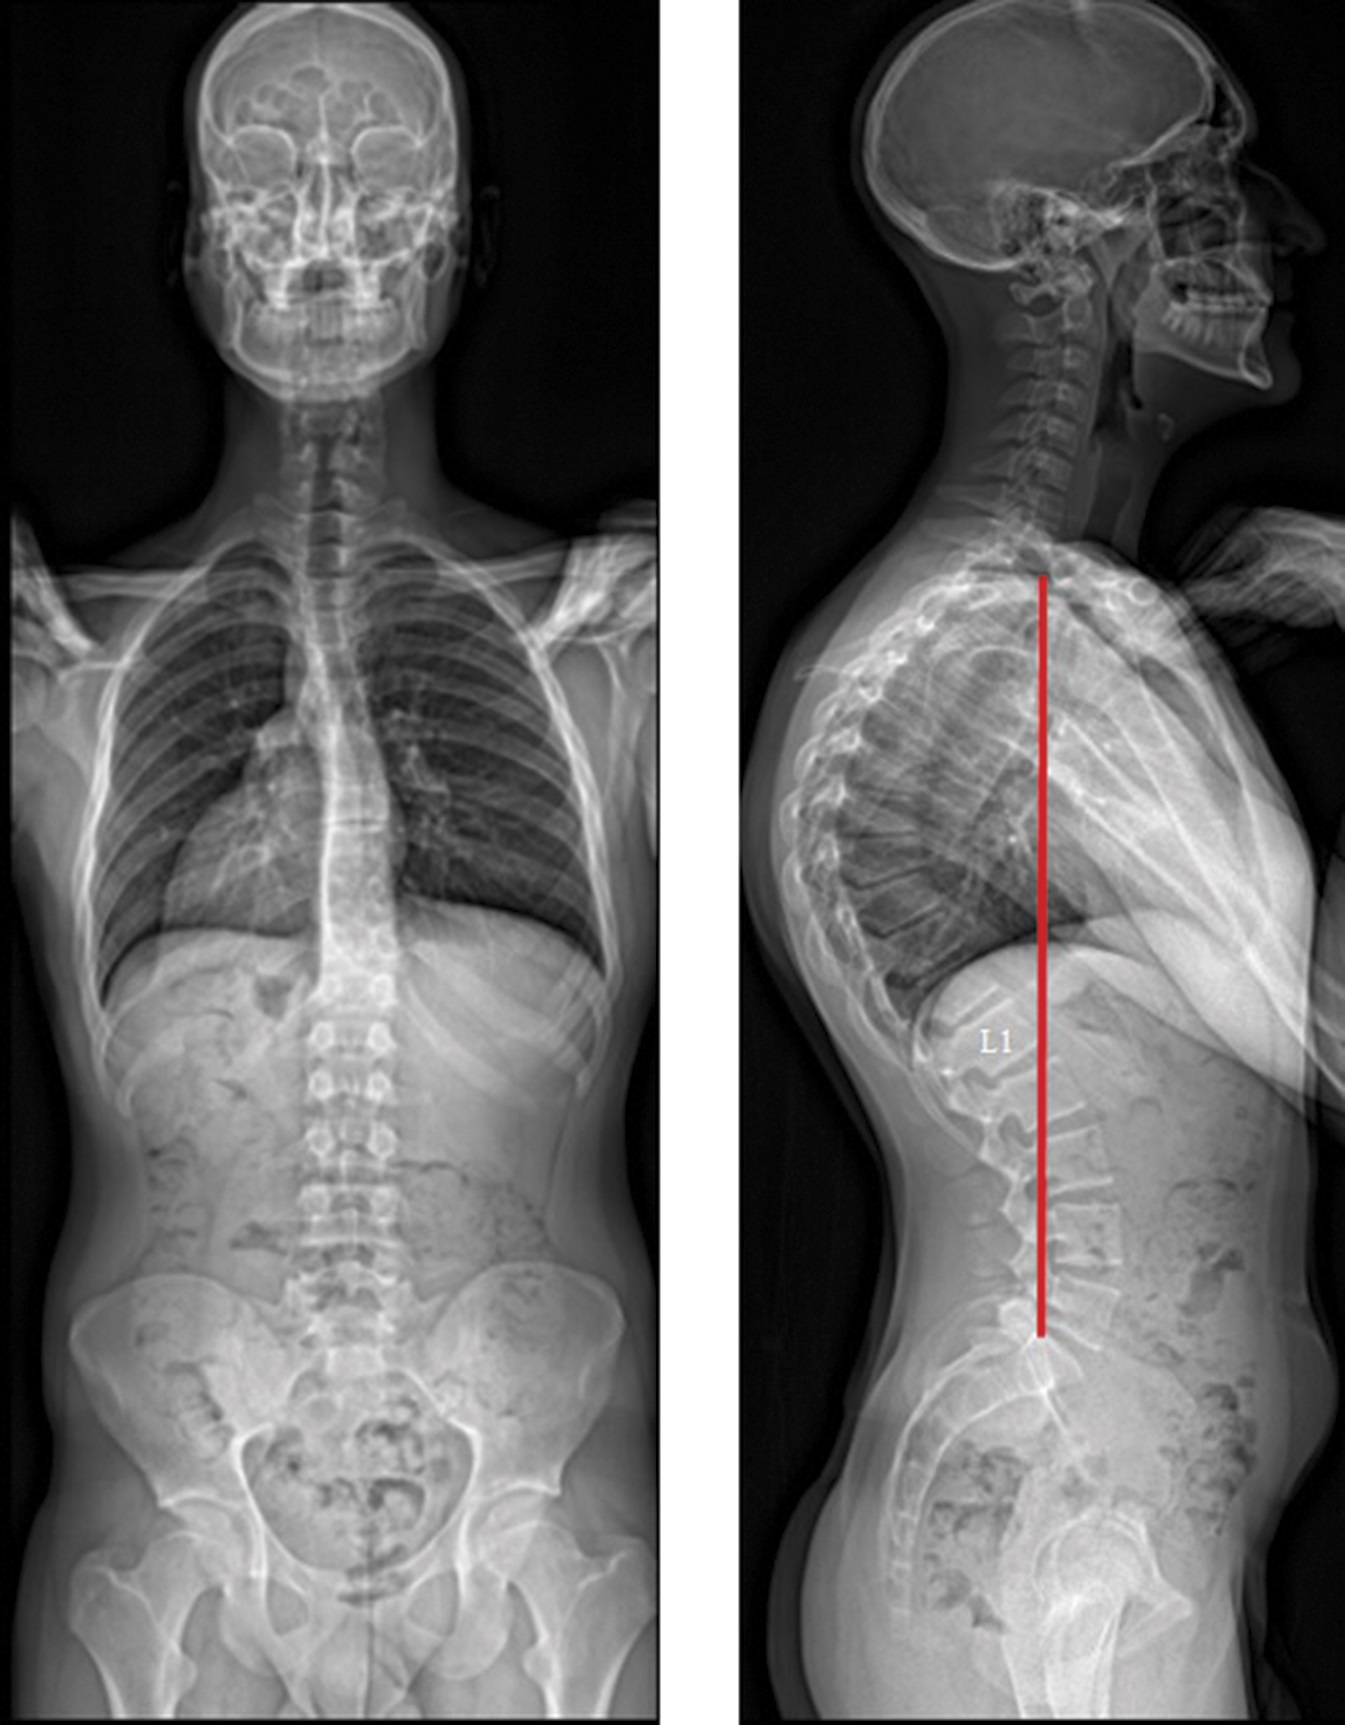

X-ray showing thoracic kyphosis measuring 82 degrees

X-rays showing thoracic kyphosis measuring 82 degrees.